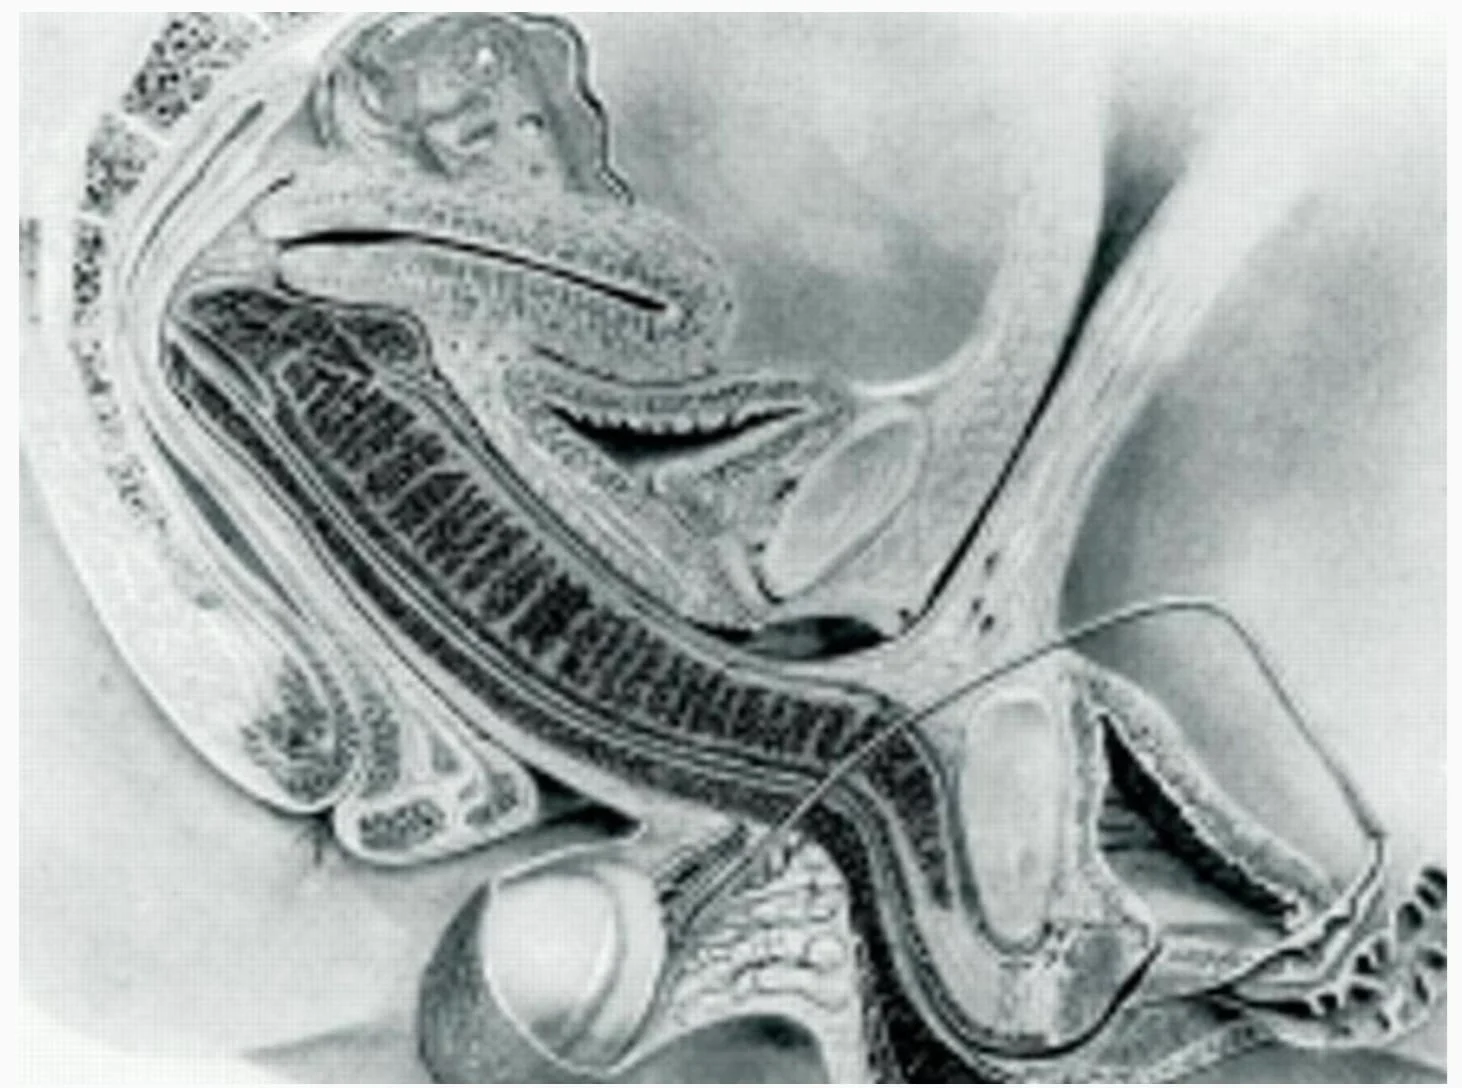

Σύμφωνα με τις μαγνητικές τομογραφίες από το πείραμα, κατά τη διάρκεια της σεξουαλικής επαφής, το ανδρικό μόριο δεν παραμένει ευθύ. Αντιθέτως, καμπυλώνεται προκειμένου να προσαρμόζεται στο σχήμα του γυναικείου κόλπου– σε αντίθεση με όσα υποστήριζαν παλαιότερες θεωρίες, που φτάνουν πίσω στην εποχή του Λεονάρντο ντα Βίντσι.

Η μελέτη διαπίστωσε ότι το πέ:ος λυγίζει σαν μπούμερανγκ κατά τη διάρκεια της πραξης.

Ο κόλ:πος δεν είναι τόσο ευθύς όσο πιστευόταν προηγουμένως πριν από τη μελέτη.